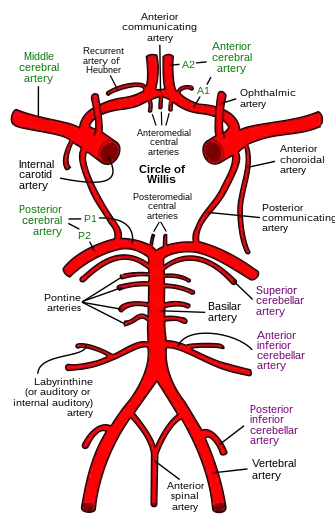

The cerebral arteries describe three main pairs of arteries and their branches, which perfuse the cerebrum of the brain. The three main arteries are the:

- Anterior cerebral artery (ACA), which supplies blood to the medial portion of the brain, including the superior parts of the frontal and anterior parietal lobes[1]

- Middle cerebral artery (MCA), which supplies blood to the majority of the lateral portion of the brain, including the temporal and lateral-parietal lobes.[2][3] It is the largest of the cerebral arteries and is often affected in strokes[4]

- Posterior cerebral artery (PCA), which supplies blood to the posterior portion of the brain, including the occipital lobe, thalamus, and midbrain[5]

Both the ACA and MCA originate from the cerebral portion of internal carotid artery, while PCA branches from the intersection of the posterior communicating artery and the anterior portion of the basilar artery. The three pairs of arteries are linked via the anterior communicating artery and the posterior communicating arteries. All three arteries send out arteries that perforate brain in the medial central portions prior to branching and bifurcating further.

The arteries are usually divided into different segments from 1–4 or 5 to denote how far the level of the branch with the lower numbers denoting vessels closer to the source artery. Even though the arteries branching off these vessels retain some aspect of constancy in terms of size and position, a great amount of variety in topography, position, source and prominence nevertheless exists.[6][7]